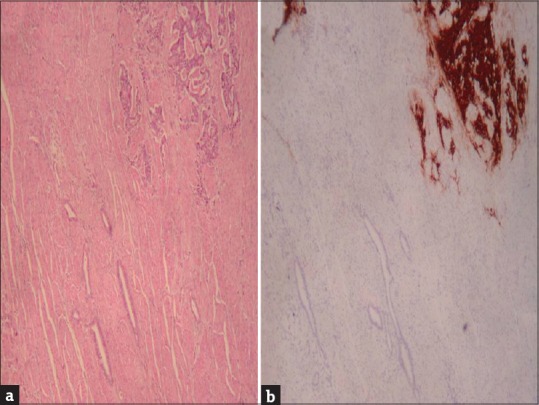

食管癌最常见的表现是腺癌和鳞状细胞癌。近年来,后者的发病率有所下降,增加了腺癌的发病率。目前,另一种发病率低得多的肿瘤被描述为具有神经内分泌成分和另一种外分泌腺成分的肿瘤,自2010年以来被归类为混合性腺神经内分泌癌(MANEC)。我们提出的情况下,68岁的男性消化不良和胃脘痛的历史后,进行胃镜检查,被诊断为恶性肿瘤的食道。患者行全食管切除术,经颈吻合术重建胃管状成形术。免疫组化后的最终结果显示,肿瘤由60%的腺癌成分和40%的与神经内分泌相容的成分组成。根据这些发现并根据世界卫生组织2010年的分类被诊断为食道MANEC。manec是一种罕见的肿瘤,发生在消化道的其他部位,食道是一个罕见的位置。其术前诊断困难,需要通过特异性免疫组织化学技术对完整片进行最终分析才能确定诊断。它的治疗基本上是手术,而化疗辅助治疗方案由于发病率低,目前还没有很好的定义。

The most frequent presentation of esophageal cancer is adenocarcinoma and squamous cell carcinoma. In recent years, the latter has decreased its incidence increasing the adenocarcinoma. Currently, another type of tumor with a much lower incidence has been described, which has a neuroendocrine component along with another exocrine glandular component and has been classified since 2010 as mixed adenoneuroendocrine carcinoma (MANEC). We present the case of a 68-year-old male with a history of dyspepsia and epigastric pain who after performing a gastroscopy, was diagnosed with a malignant neoplasm of the esophagus. The patient underwent a total esophagectomy with reconstruction by tubular gastroplasty with cervical anastomosis. The final result of the piece after immunohistochemistry revealed that the tumor was composed of one component of adenocarcinoma in 60% together with another component compatible with neuroendocrine in 40%. With these findings and according to the World Health Organization classification of 2010 was diagnosed as esophageal MANEC. MANECs are rare tumors, described in other locations of the digestive tract, the esophagus being an infrequent location. Its preoperative diagnosis is difficult, and it is not until the final analysis of the complete piece by means of specific immunohistochemical techniques when its diagnosis can be established. Its treatment is fundamentally surgical, whereas the adjuvant therapeutic schemes with chemotherapy are not well defined at present because of their low incidence.